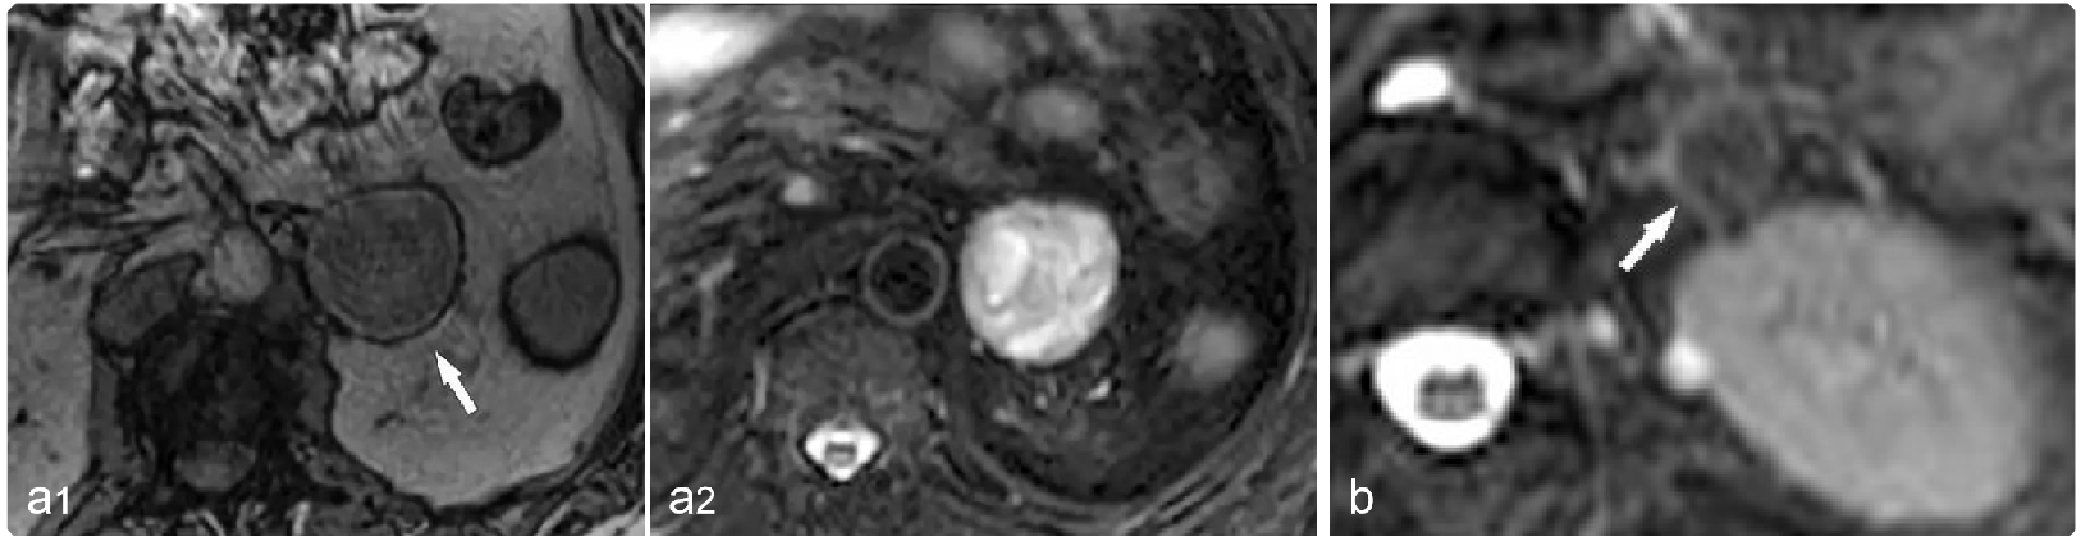

59b3732e0785f667336ea7dc317ef2cc.png

病例 3:粘液型脂肪肉瘤  68岁男性,腹痛3个月,逐渐加重

(a, b) T2WI (a) 和T2WI-FS (b)显示盆腔肿瘤呈高信号(*),内可见花边状低信号(箭)。(c) 对比增强 T1WI-fs显示肿瘤内斑片状强化区(箭)。(d) 大体病理显示双瓣状、边界清楚的肿块,切面呈棕黄色、凝胶状,光滑闪亮(*),另见占总表面积30% 的出血区域(**),肿瘤似乎完全被薄的纤维假包膜(箭)包裹。(e) 低倍镜显示丰富的粘液样基质,其中包含纺锤形肿瘤细胞和网状的毛细血管系统(箭)(HE×100)。